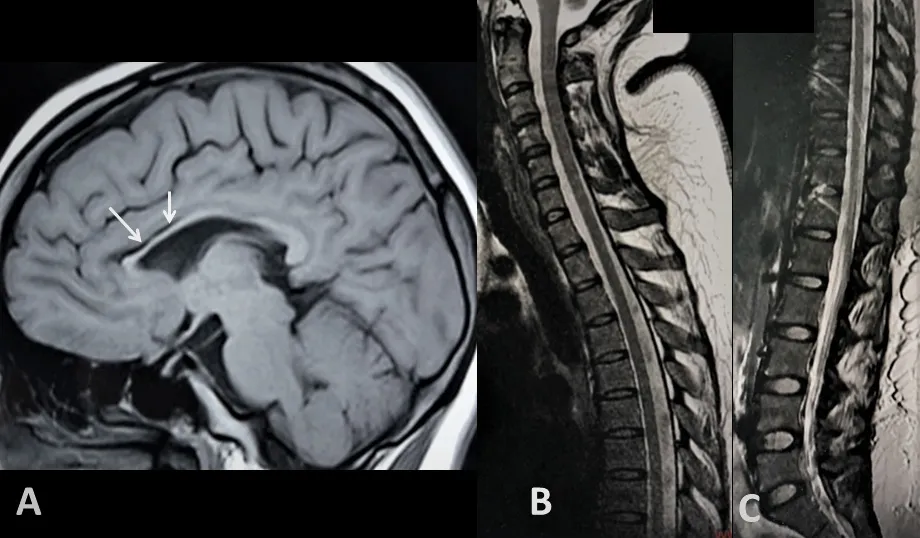

图2 脑胼胝体矢状T1加权像(A)显示整个胼胝体弥漫性变薄,且以胼胝体前部(箭头所示)为著。整个脊柱矢状T2加权序列(B、C)未见脊髓显著异常,亦无提示脊髓变薄或脊髓高信号的特征,该结果经轴位T2加权序列证实。